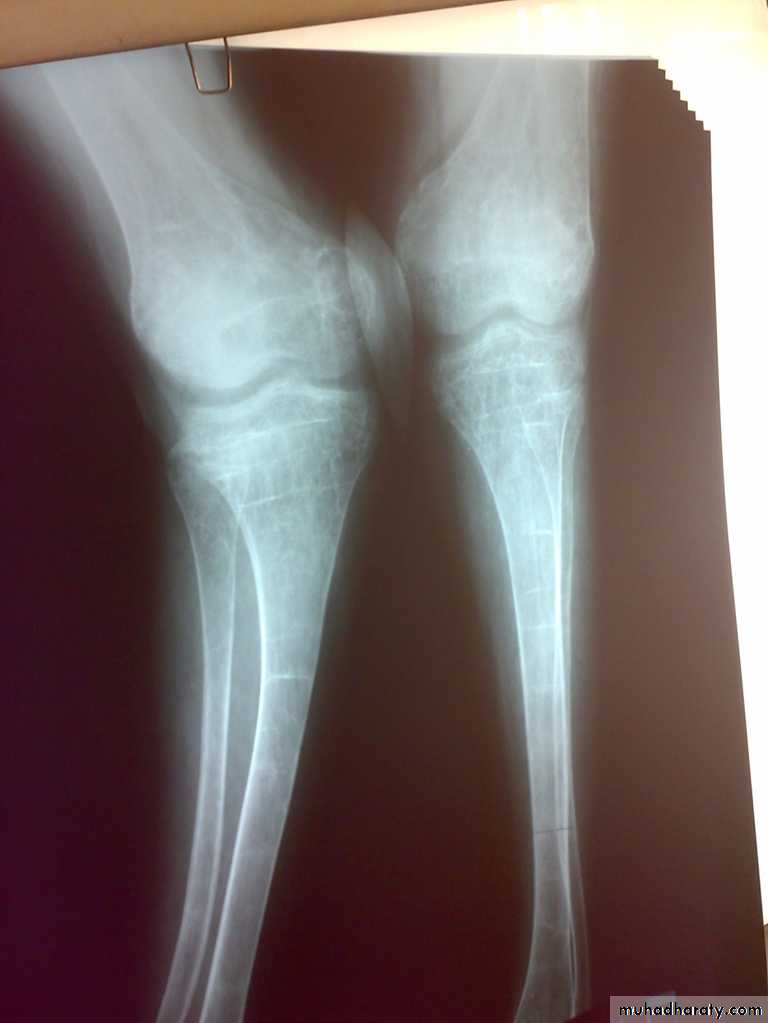

It is a clinical disorder characterized by an abnormally low bone mass and defects in bone structure, render the bone fragile.

A state in which bone is fully mineralized but its structure is abnormally porous and its strength is less than normal person of that age and sex

OSTEOPOROSIS Reduction of normally mineralized bone mass per volume.

It may result from increased bone resorption or

decrease bone formation or both.Osteopenia: bone which appears to be less dense than normal X-ray.

Any density reduction in DEXA more than 2.5 standard deviation define as osteoporosis.

Between 1-2.5 name osteopenia

4- Osteoporosis is common cause of fractures especially femoral neck fractures , vertebral fractures and distal radial fractures .